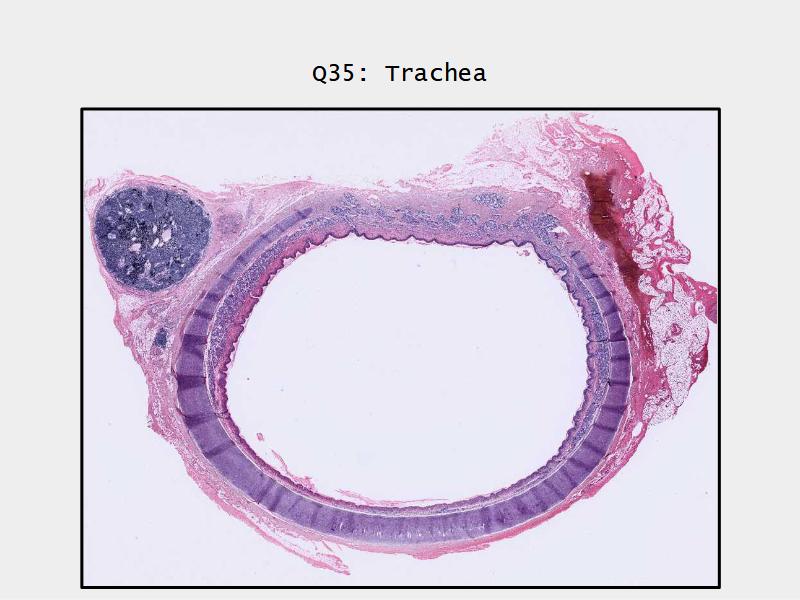

Trachea

Respiratory epithelium

- Pseudostratified

- Ciliated

- Columnar

- Epithelium with

- 4 Cells

- Ciliated columnar cells

- Non-ciliated columnar cells

- Goblet cells

- Basal cells